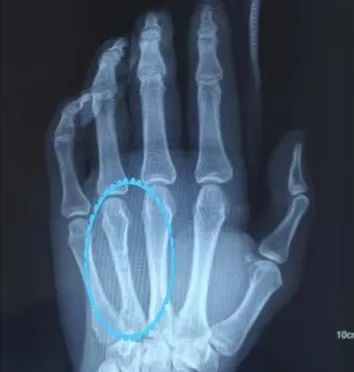

这名年轻男性患者因“左侧第四掌骨骨折”寻医问诊,因顾虑二次手术取出固定钢板还要再痛一次,就到处询问偏方,毕竟痛的事情一次就够了,不要再来一次。可是哪里不受皮肉之痛呢?还是咬牙坚持吧!

最终采用微创手术切口,有限切开骨折复位,用可吸收接骨板及螺钉固定……此处省略千余字手术过程。

术前 术后